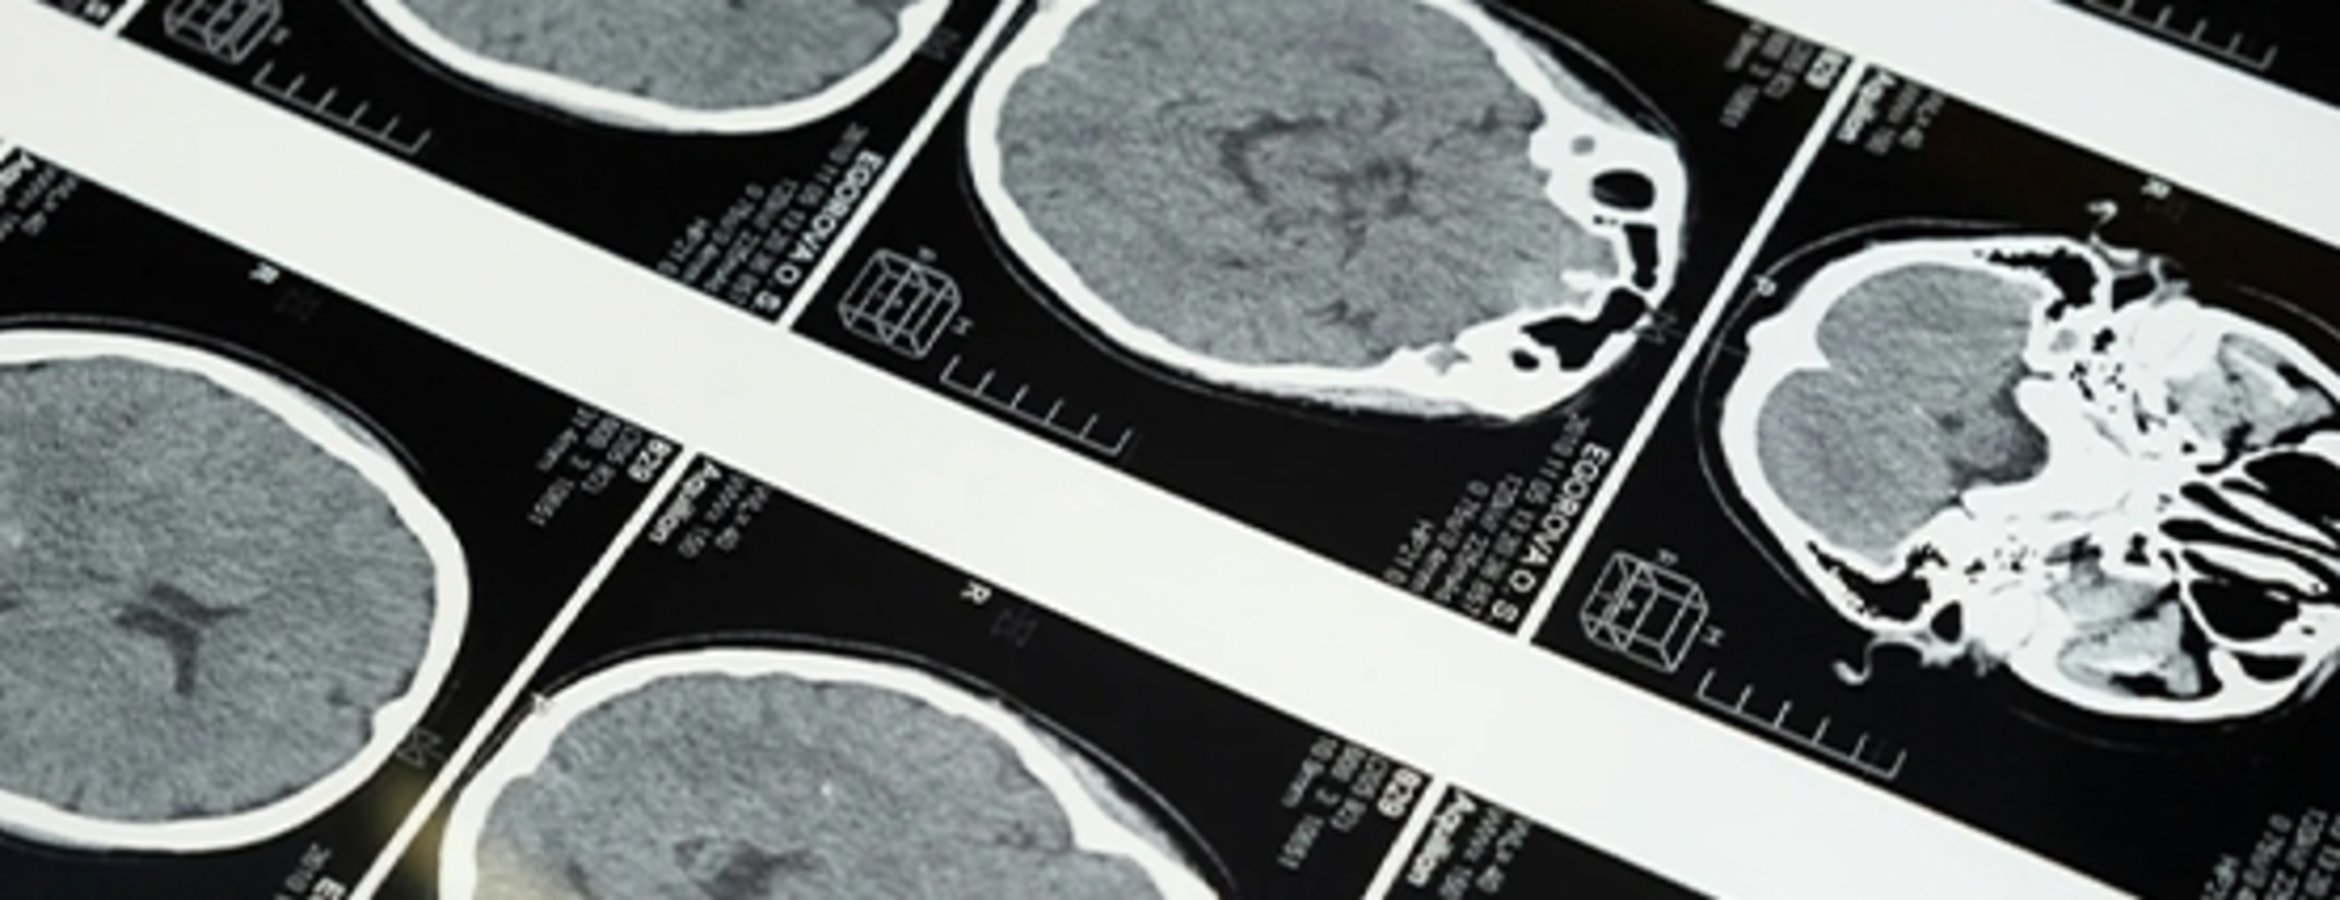

Konuşma bozukluğu inme habercisi olabilir

Uzamanlara göre dünyada en sık görülen üçüncü ölüm nedeni olan inmenin, yüzde ani kayma, kol veya bacakta güçsüzlük ve konuşma bozukluğu gibi belirtilerle ortaya çıkabileceğini belirtti.

Hastaneden yapılan açıklamada görüşlerine yer verilen Asil, dünyada en sık görülen üçüncü ölüm nedeni olan inmenin, yüzde ani kayma, kol veya bacakta güçsüzlük ve konuşma bozukluğu gibi belirtilerle ortaya çıkabileceğini belirtti.